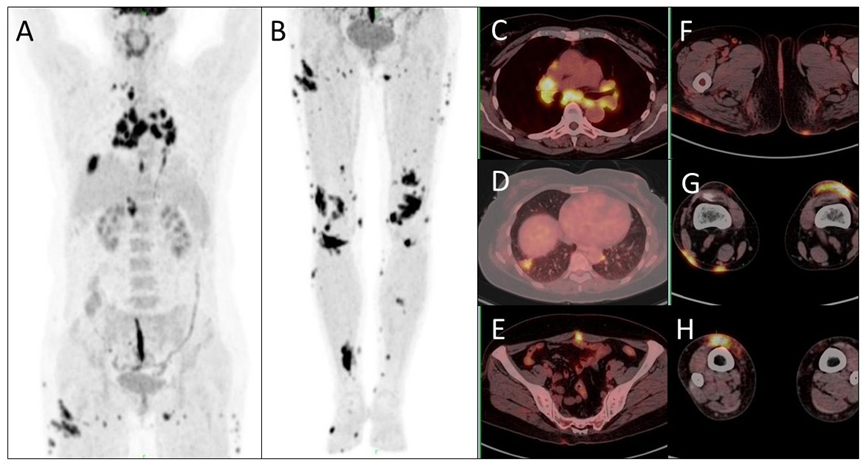

病例(2为一中年女性,因体检发现纵隔淋巴结肿大就诊,既往因“子宫肌瘤”行子宫切除术;胸部增强CT示纵隔及双肺门多发肿大淋巴结,增强扫描呈均匀明显强化,右肺下叶见斑片状实变灶;18F-FDG PET/CT示右侧锁骨上区、纵隔、双肺门、肝门区及双侧腹股沟多发大小不等淋巴结伴代谢增高,右肺下叶斑片灶代谢增高,下腹部中线手术切口区代谢增高,双臀部、下肢皮下少许软组织密度灶伴代谢增高;患者行超声支气管镜下纵隔淋巴结穿刺活检,病理为肉芽肿性炎形成,临床最终诊断为结节病(Sarcoidosis)。